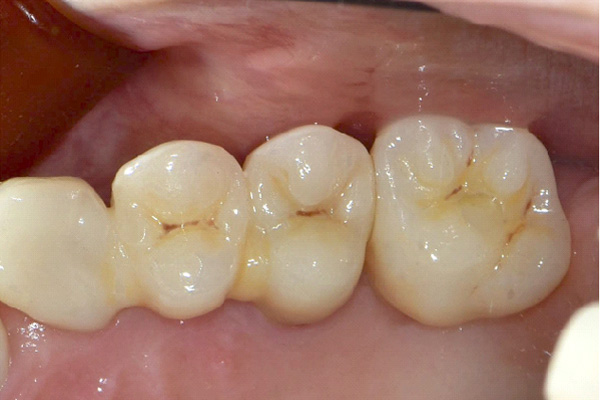

| 年代・性別 | 50代 男性 |

|---|---|

| 主訴 | 右下の歯がないのでインプラントをして欲しい |

| 治療期間 | 約6ヶ月 |

| 費用 | 600,000円 |

| 治療内容 | インプラント、骨造成、結合組織移植、セラミック修復 |

| 治療に伴うリスク | インプラント周囲炎 セラミックの破折、脱離 |

*キャンセルポリシーをご一読のうえご予約ください